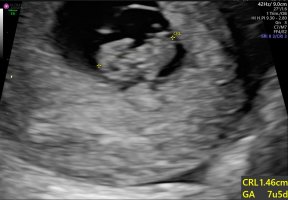

Det kan jeg heller ingenting om, men det hadde vært noeFantastisk! Da kan mammahjertet slappe litt av.En sprell levende 9+3 uker gammel elskling!!! Etter en helvetes helg med så mye vondt og blødninger. Jeg er så lykkelig !!

Har også drømt om at jeg fikk tvillinger, så fint å få bekreftet at det kun er en inni derPrivat ul i dag, 9+3. Han nevnte både 9+2 og 9+4 etter han målte, så tror menstermin er rimelig spot on. Hjertet slo, fikk høre og alt! Deilig å få en belreftelse, etter å ha lest om sa og ma her inne blir man jo litt smårar... Absolutt verdt pengene for min del, en fin bursdagsgave til meg selv